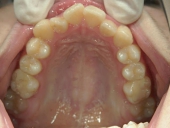

舌側プチワイヤー矯正/上顎のみ 症例(2)

13歳 女性 袋井市在住 治療期間 1年

矯正歯科 治療前 上顎